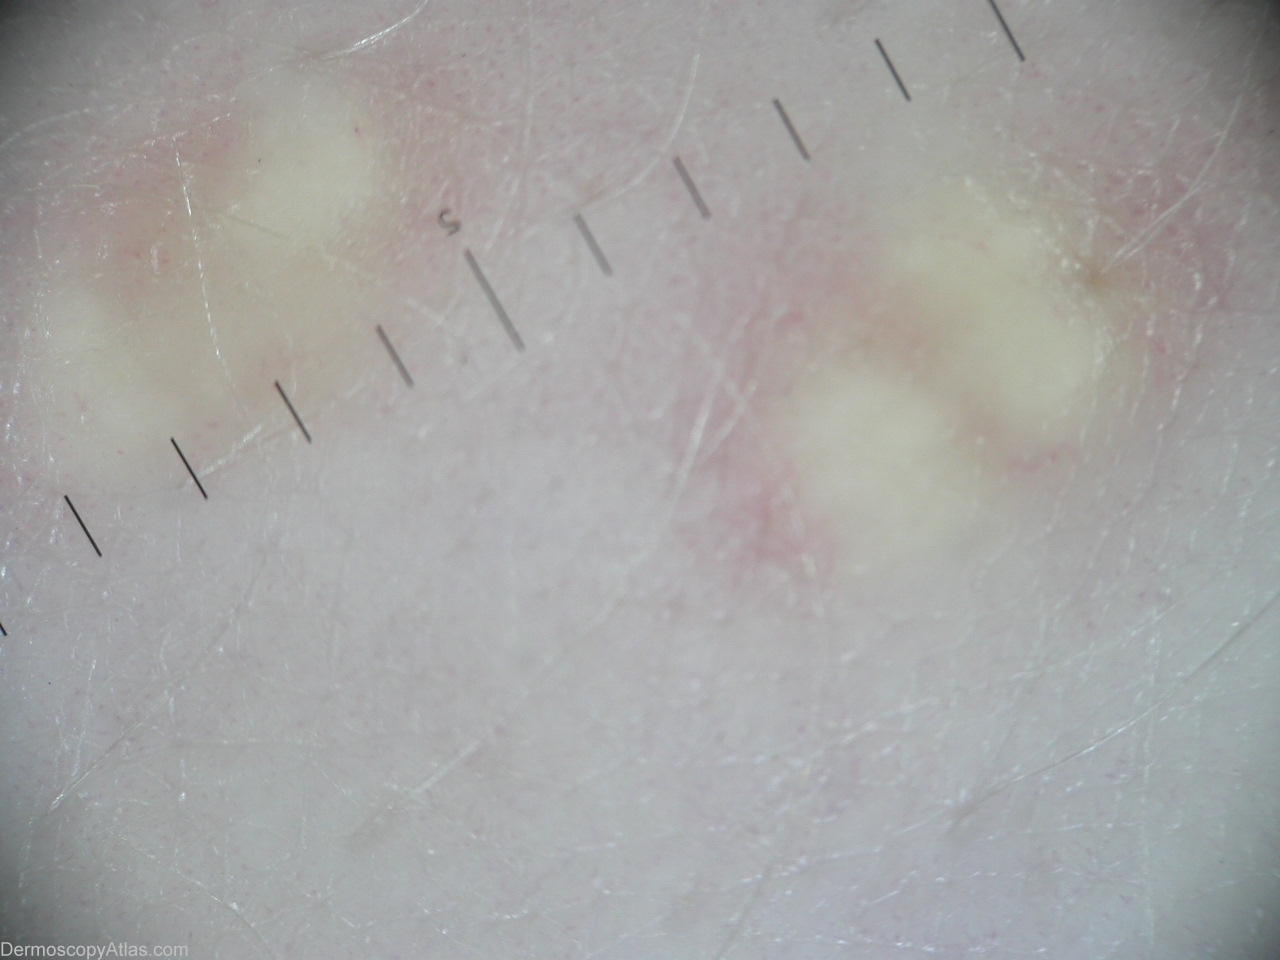

Diagnosis: Eruptive xanthoma

Description: Orange-yellow ('setting sun'); homogenous structure.

History: A 31 year old man developed eruptive xanthomas over all his body since 3 years ago. Dermoscopic description:Orange-yellow ('setting sun') homogenous structure.